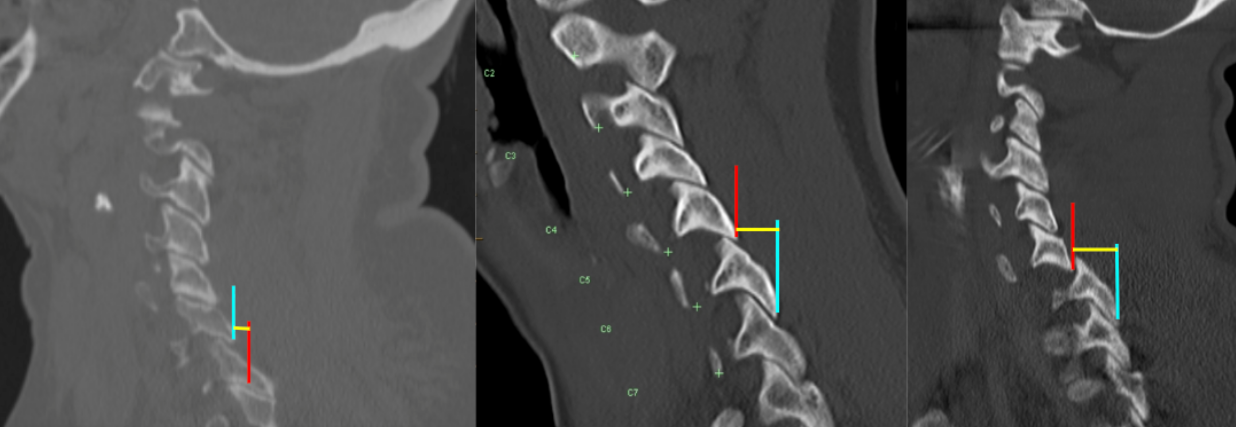

Facet joint step-off quantifies the anteroposterior displacement between articulating cervical facet joints and is used to identify facet subluxation, perched facets, and locked (jumped) facets, which represent progressively severe forms of posterior element instability.

This measurement assesses the degree of malalignment between the inferior articular facet of the superior vertebra and the superior articular facet of the inferior vertebra. Increasing step-off distance reflects escalating mechanical instability and is strongly associated with disco-ligamentous injury, neurologic risk, and the need for surgical stabilization.

• Draw two vertical reference lines along these posterior cortical margins.

• Measure the horizontal anteroposterior distance (mm) between the two lines:

• This distance represents the facet joint step-off.